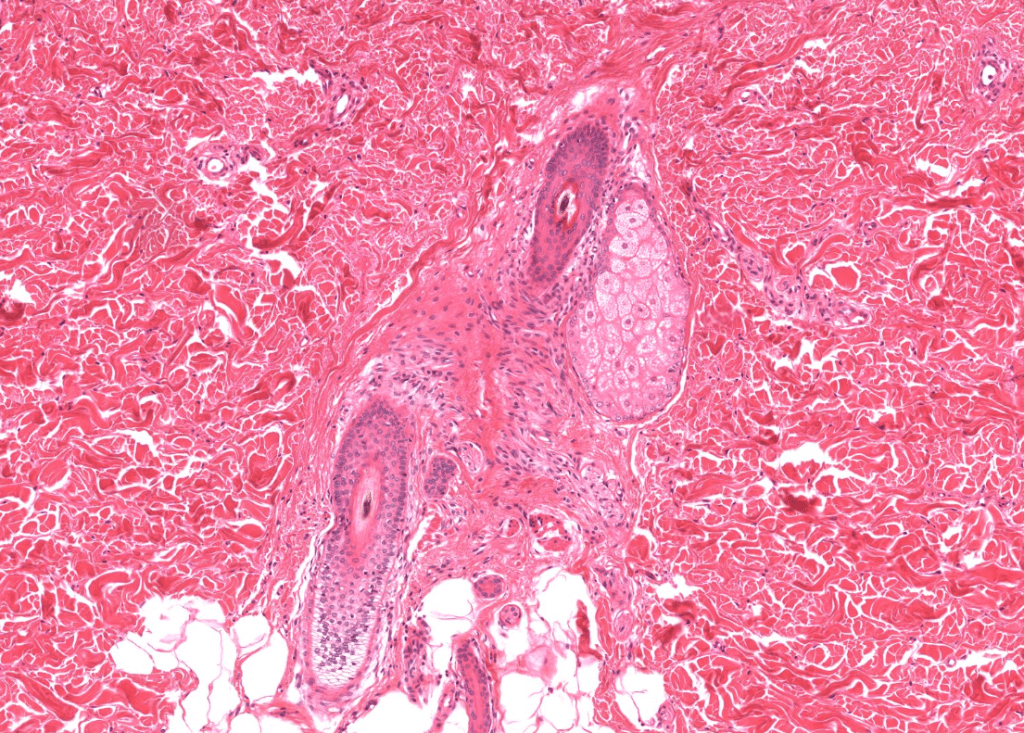

SUDORÍPARAS APOCRINAS

Ubicadas en ano, areola, axila.

«TRIPLE A»

SÍ se asocian a folículos pilosos.

Glándulas especiales: de Moll (párpados), ceruminosas (oído), gl. mamaria lactante.